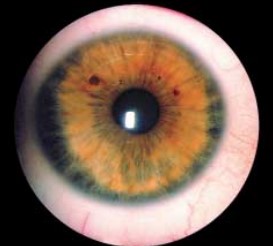

Эта своеобразная форма глаукомы встречается у лиц молодого возраста и характеризуется гипоплазией стромы радужек с обнажением ее пигментного эпителия. Уже при рождении ребенка отмечается наиболее яркий клинический признак заболевания — контрастная двухцветная окраска радужки. Процесс всегда двусторонний.

У всех без исключения пациентов обращает на себя внимание своеобразный вид радужной оболочки:

- Зрачковая зона радужки шире ресничной и выглядит как сероватое или желтое кольцо с ровной либо ватообразной поверхностью.

- Ресничная зона за счет обнажения пигментного листка имеет значительно более темный шоколадно-коричневый или сине-лиловый цвет.

- В прикорневой части ресничной зоны может отмечаться желтовато-оранжевого цвета недифференцированная губчатая мезодермальная ткань.

- По мере развития заболевания в пигментном листке появляются и прогрессируют сквозные дефекты, приводя в тяжелых случаях к аниридии с визуализацией неизмененных цинновых связок.